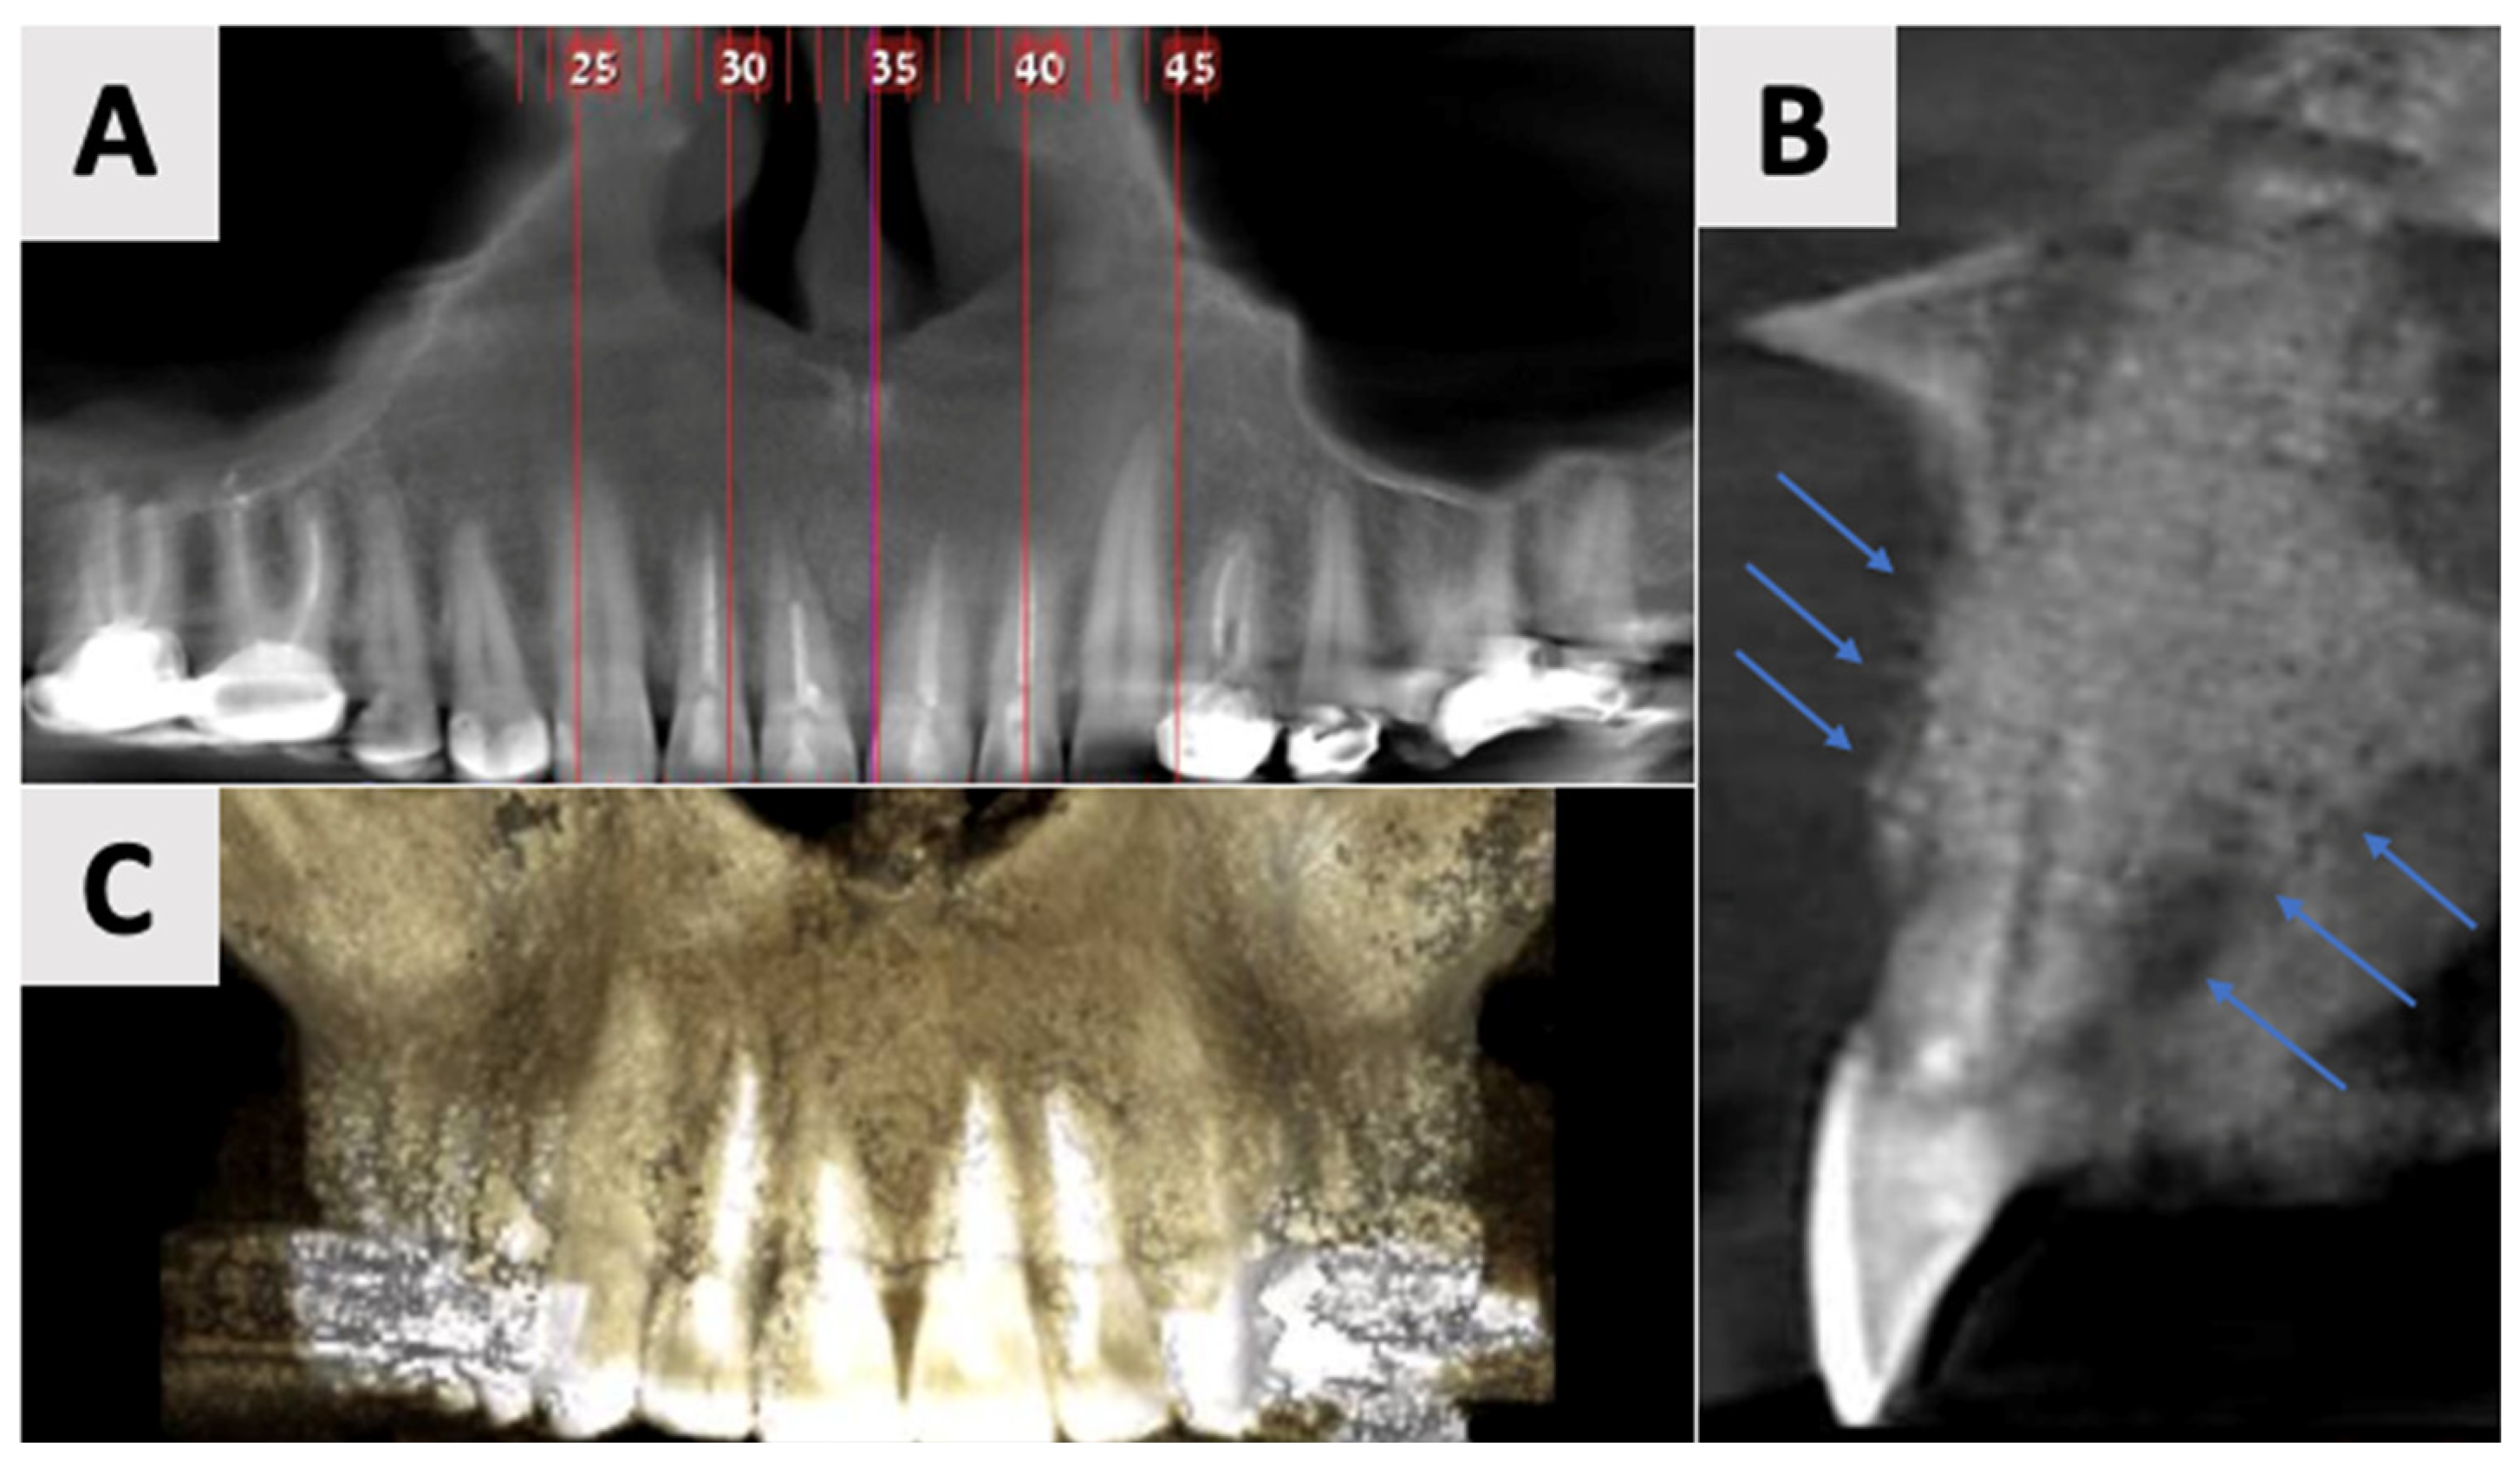

The follow-up examinations at 2 and 16 months post-augmentation revealed favorable bone and soft tissue healing outcomes. CBCT scans were performed at both time points. At the 2-month follow-up, CBCT imaging demonstrated initial bone formation within the augmented site (Figure 6).

Figure 6.

CBCT imaging analysis 2 months post-augmentation. (A) Panoramic reconstruction showing the overall healing of the defect site. (B) The restored contour of the facial and palatal bony walls (blue filled lines). (C) Paraxial view showing the initial osseous regeneration.

By the 16-month mark, significant improvements in bone volume and density were observed (Figure 7). The palatal contour was restored to its proper anatomical form, with notable cortication of the palatal wall. Importantly, there was no evidence of pathological recurrence around the treated teeth. The buccal entry point for the previously placed rubber dam had healed completely, with cortical bone formation.

Figure 7.

CBCT evaluation of bone regeneration at 16 months post-treatment. (A) Panoramic reconstruction showing the absence of radiolucency in the region of prior cyst drainage, indicating a complete osseous integration. (B) Three-dimensional paraxial reconstruction illustrating comprehensive bone regeneration throughout the defect site, with restoration of anatomical contours. (C) Serial axial CBCT slices (through the affected teeth) demonstrate complete reconstruction of both buccal and palatal bony walls, characterized by the presence of distinct cortical bone layers.

Clinical examination at 16 months post-augmentation revealed that the patient remained asymptomatic. The treated teeth exhibited no mobility. Both the alveolar bone and soft tissue contours were well-maintained, preserving the site’s architecture (Figure 8). The patient reported no functional limitations or esthetic concerns, further confirming the success of the procedure from both clinical and patient-centered perspectives.

The use of CBCT has revolutionized the diagnosis, treatment planning, and follow-up of large periapical lesions. In comparison to traditional periapical radiographs, CBCT offers superior characteristics in assessing lesion characteristics and monitoring healing progress [41,42]. CBCT examination allows for more accurate measurements of lesion boundaries in all three planes, providing a comprehensive view of the defect’s extent and its relationship to surrounding anatomical structures. In our case, CBCT imaging revealed the true size of the lesion and the extent of palatal bone wall erosion, factors that were crucial for our treatment plan (Figure 1). The healing process of periapical lesions with bone destruction follows a predictable pattern, starting from the periphery and progressing towards the center [43]. This healing is characterized by a gradual reduction in lesion size due to new bone formation. Complete healing, including the restoration of the periodontal ligament architecture around all root contours, can take anywhere from one to four years [44,45]. In our case, follow-up CBCT examinations at 2 and 16 months (Figure 7 and Figure 8) post-treatment confirmed this staged progress in bone regeneration. The 2-month CBCT showed initial bone formation within the augmented site, while the 16-month scan demonstrated improvements in bone volume and density, with the restored palatal contour and cortication of the palatal wall.